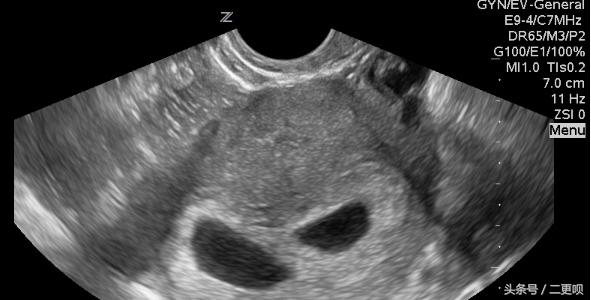

附上当时孕7周的B超单

孕7周B超单